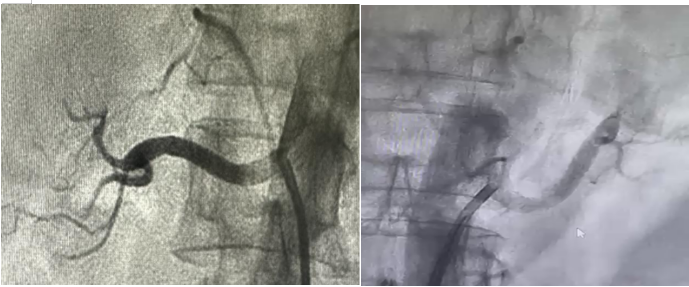

术中,确认镇静镇痛药物起效后,曙光医院医疗团队小心翼翼地在冯女士的股动脉(大腿根部的一条重要血管)处进行穿刺,就像用细针轻轻扎一下,然后放入一个鞘管,鞘管就像是一个“通道”,方便后续的操作。通过这个鞘管,医生送入一根细细的导管,利用这根导管给肾动脉做个“透视检查”,也就是肾动脉造影。这就像是给血管拍一张清晰的照片,让医生能清楚地看到肾动脉的形状、有没有堵塞或者异常等情况。

(左肾造影) (右肾造影)